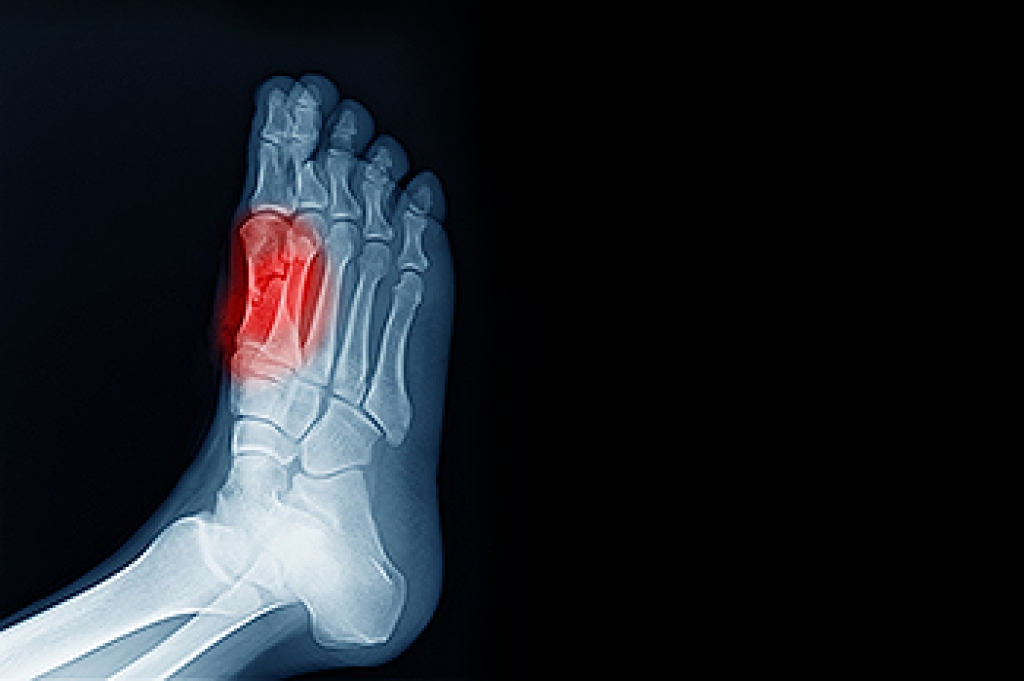

Fractures in the Foot or Ankle During Childhood

Foot and ankle fractures are fairly common in children, especially those who are active in sports or play. These injuries happen when one or more bones break due to a fall, twist, or direct hit. Signs may include swelling, bruising, trouble walking, or the child refusing to put weight on the foot. Because children’s bones are still growing, some fractures affect growth plates, which are areas near the ends of bones that help shape future bone development. Treatment depends on the location and severity of the break. Some injuries may heal with rest, a cast, or a boot, while others may need more involved care to make sure the bones heal in the correct position. If your child has foot or ankle pain after an injury, it is suggested that you see a podiatrist to make sure proper healing can begin.

Broken Foot Causes, Symptoms, and Treatment

A broken foot is caused by one of the bones in the foot typically breaking when bended, crushed, or stretched beyond its natural capabilities. Usually the location of the fracture indicates how the break occurred, whether it was through an object, fall, or any other type of injury.

Those that suspect they have a broken foot shoot seek urgent medical attention where a medical professional could diagnose the severity.

Treatment for broken bones varies depending on the cause, severity and location. Some will require the use of splints, casts or crutches while others could even involve surgery to repair the broken bones. Personal care includes the use of ice and keeping the foot stabilized and elevated.